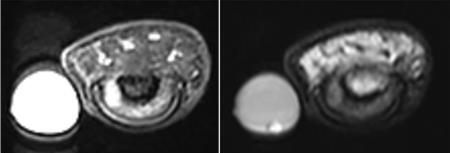

A 58 year Female presented with C/o right middle finger pain and tenderness.

Since the mass is usually very small in size, it is very difficult to palpate. Hence, MRI is the imaging modality of choice. Contrast MRI has a significant role in the diagnosis of glomus tumors.

Early tumor recognition allows surgical resection that completely resolves the crippling, chronic pain associated with these lesions.